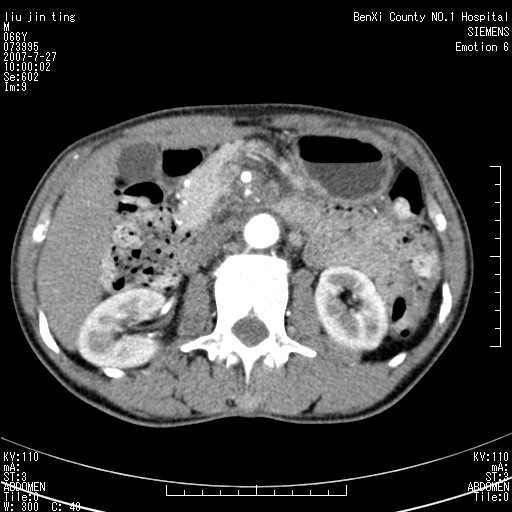

腹痛,背痛,无恶心呕吐,不黄,彩超示胰腺钩癌,ct扫描病灶平扫30-40hu,增强后动脉期40--60hu,静脉期50-68hu,真的是钩突上的么?您要试一试么?

动脉期

静脉期